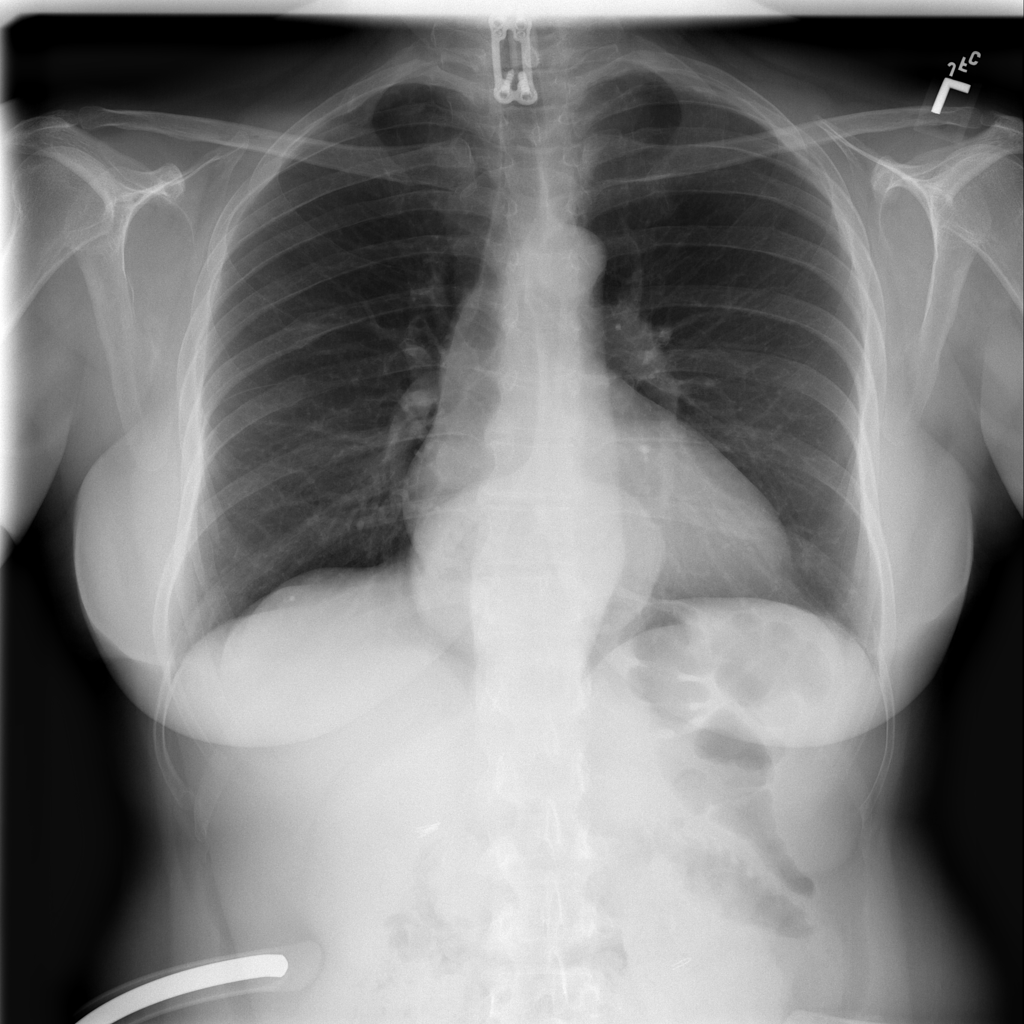

PAT-C048 · IMG-001Hernia

PAT-C048 · IMG-001

PA